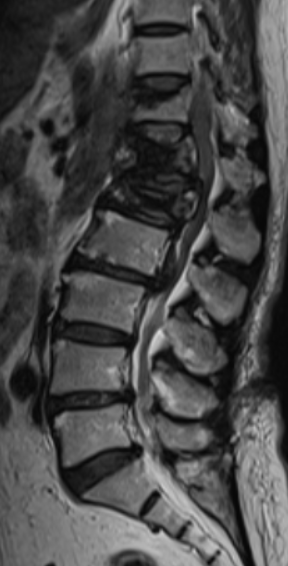

Hơn 10 năm kinh nghiệm Phẫu Thuật các bệnh lý Thoát Vị Đĩa Đệm; Tạo Hình Đốt Sống Bằng Cement Sinh Học; Nội soi cột sống, Phẫu thuật cột sống xâm lấn tối thiểu.